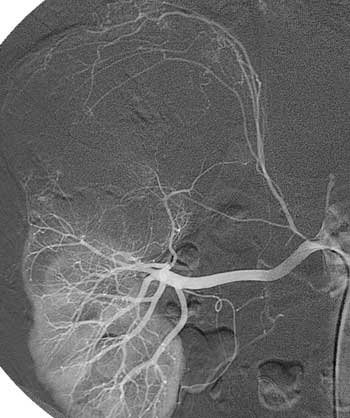

Рис. 8. Рак правой почки. Т3аN0M0. Гиповаскулярная опухоль в проекции которой в артериальную фазу ангиографии визуализируются единичные опухолевые сосуды.